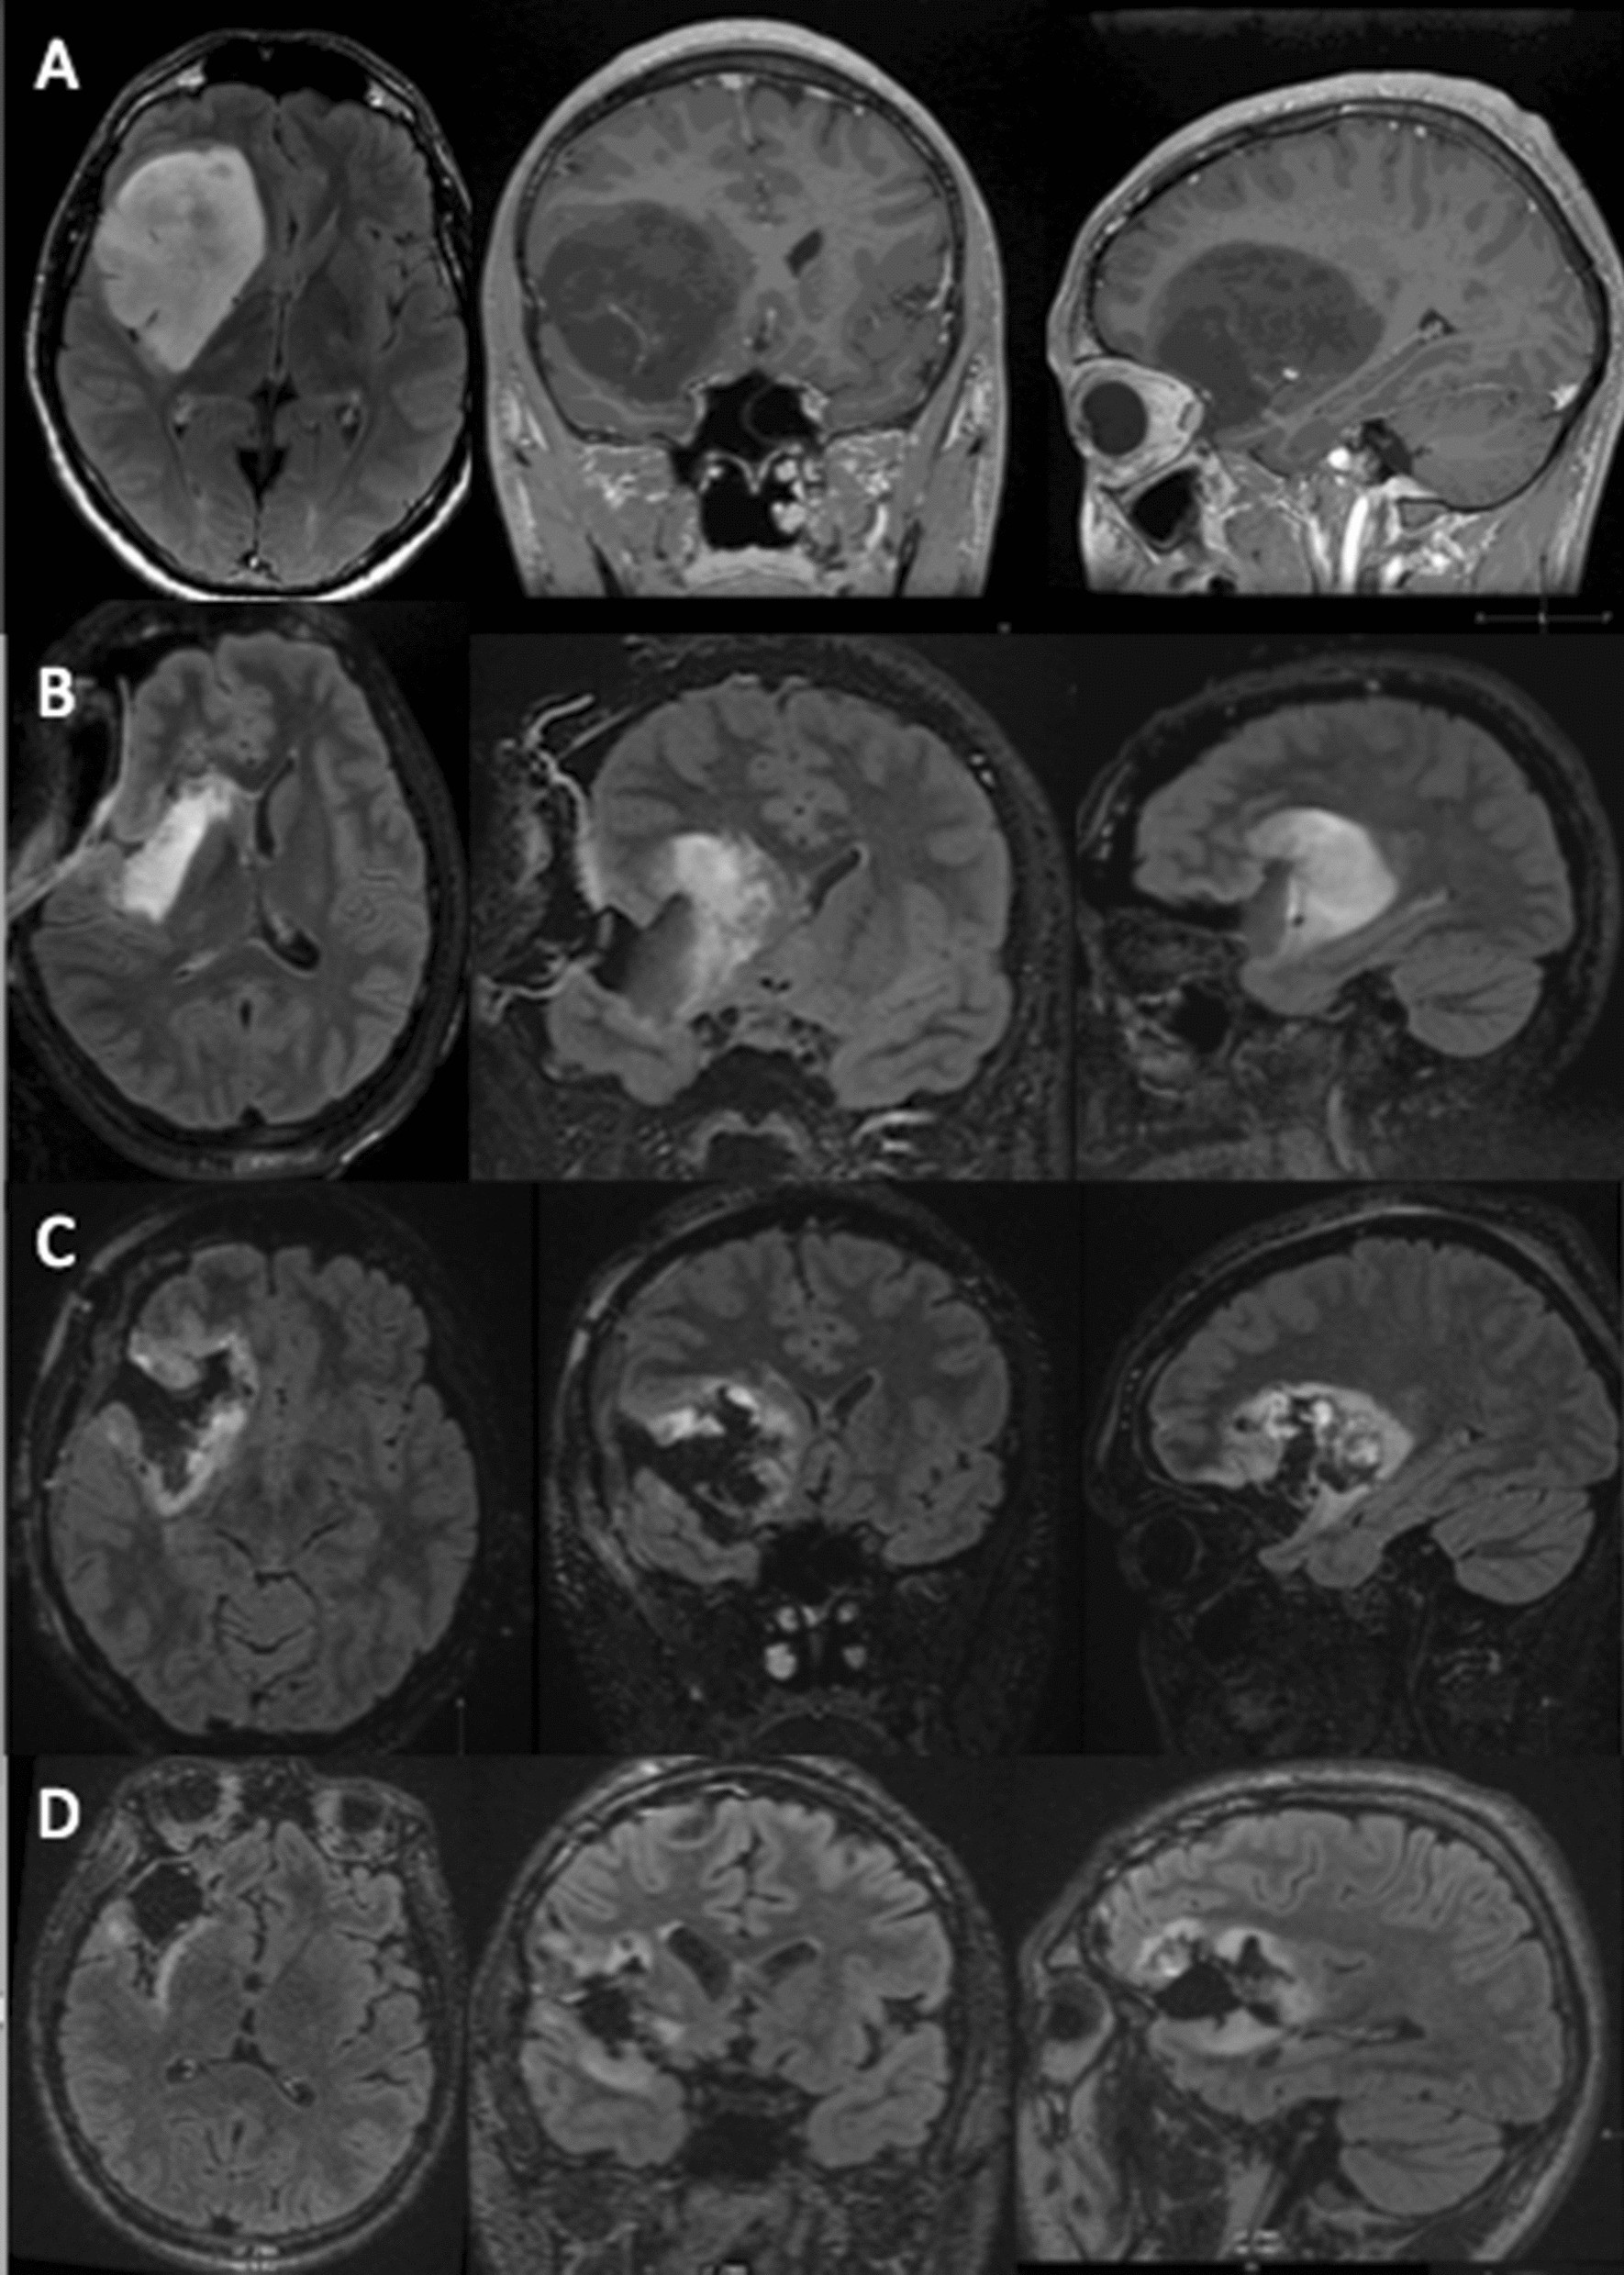

Figure 3

Staged surgical approach for a right fronto-temporo-insular glioma. (A) Preoperative MRI depicting a hypo signal T1 lesion, with sharp contours. The preoperative volume was of 112 cm3. (B) 1st IoMRI reporting a tumor remnant at the inner and posterior part of the insula and in the frontal lobe of 38 cm3. Additional resection was performed. (C) 2nd IoMRI, the tumor residue was of 11 cm3. Due to the presence of the internal capsule at the superior part of the lesion the end of surgery was decided. (D) Postoperative control at 3 months, with less perioperative signal abnormalities the residue was reassessed, with a volume of 6 cm3, corresponding to an EOR of 95% (using IntelliSpace Portal, Philips, module “tumor tracking.” version 9.0 (www.philips.fr).